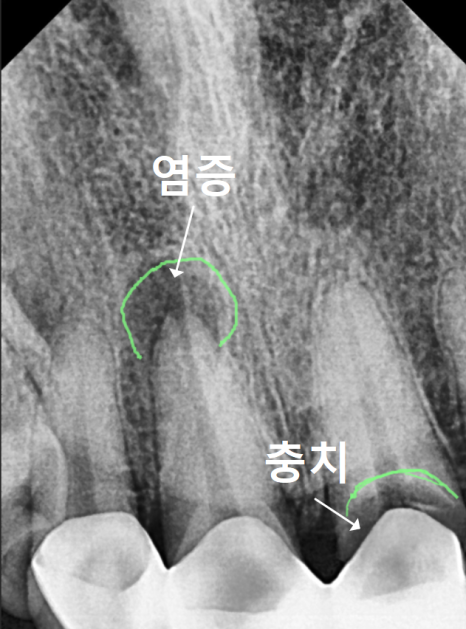

금이나 도자기로 씌운 치아는

엑스레이를 찍어도 이렇게 하얗게 나와요.

즉, 내부가 투과되지 않습니다.

그래서 안쪽에 충치가 얼마나 진행되었는지

정확히 파악하기가 힘들 수 밖에 없어요.

대부분 보철 치료를 하기 전에

신경치료를 병행하는 경우가 많은데요~

치아의 신경이 없다 보니

뿌리 끝까지 썩어 들어가도

통증을 느끼지 못하고

방치하게 되는 경우가 많아요.